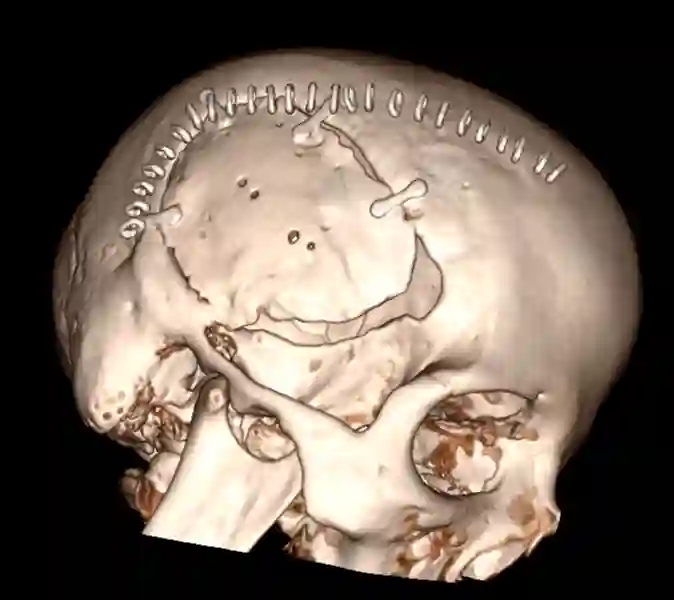

CT Rekonstruktion einer osteoplastischen Kraniotomie

CT Rekonstruktion einer osteoplastischen Kraniotomie.